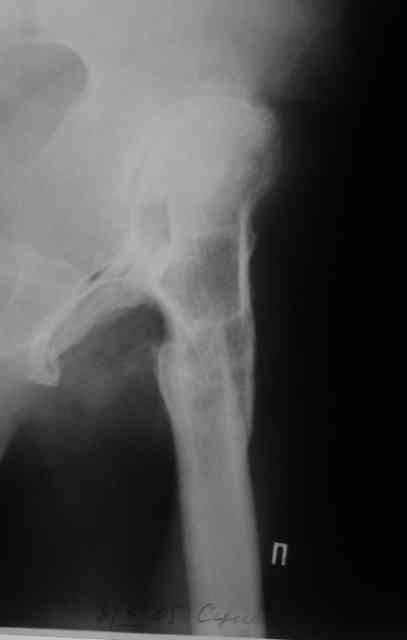

Был у нас подобный случай

Выполнена одномоментная коррекция деформации, эндопротезирование DePyu Pinnacle-AML. Пластинка с деротационной целью. При использовании ножки с прямоугольным сечением, думаю, можно и без нее.